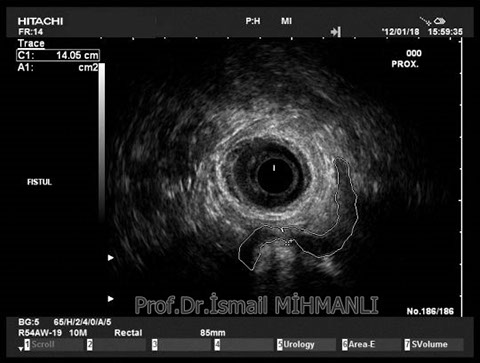

PERİANAL FİSTÜLLER Perianal fistül ve abselerin intersfinkterik anal bez iltihabından kaynaklandığı düşünülmektedir. Crohn hastalarında perianal enflamatuvar hastalık sıktır. İntersfinkterik mesafedeki enfeksiyon yukarıda rektuma, aşağıda cilde, yanlarda dış sfinkteri geçerek iskiyoanal mesafeye uzanabilir. Primer fistülün sfinkterler ile ilişkisini ve abse veya sekonder dal varlığını ameliyat öncesi bilmek, tedavi planı açısından önemlidir. İskiyoanal ve iskiyorektal mesafe tutulmamışsa hastalık daha kolay tedavi edilir. Bu mesafelerde abse veya sekonder bir dal varsa fistül komplekstir ve tedavisi kompleks olmayan fistüle göre değişik olabilir. Bundan dolayı, primer fistül traktı anatomik yerleşimine göre geleneksel olarak sınıflandırılır. Bu sınıflama dörde ayrılır: 1- İntersfinkterik (iç ve dış sfinkter arasında), 2- Transsfinkterik (dış sfinkteri geçerek iskiyoanal veya iskiyorektal mesafeye ulaşmış), 3- Suprasfinkterik (intersfinkterik plandan yukarı doğru uzanan traktüs puborektal kasın Genel Gaz ve Dışkı Kaçırma (Anal İnkontinans) Perianal Fistüller Rektal Tümörler Anal Tümörler Kabızlık Yazılarımız üstündeki bir seviyeden yana kıvrılarak tekrar aşağıya iskiyoanal mesafeye uzanmış), 4- Ekstrasfinkterik (sfinkterlerin dış tarafında rektumdan direkt olarak perianal cilde uzanan traktüs). Endoanal ultrason ile hem primer fistül, hem de varsa sekonder dal ve abse doğru bir şekilde tanınır. Endoanal ultrason ile fistülün anal kanala açılan kısmını (iç uç) görmek kolaydır. Bu hastalarda sfinkter defektlerine de rastlanmaktadır. Sfinkter defekti endoanal ultrason ile kolaylıkla tespit edilir. (bkz. anal inkontinans) Perianal fistül şikayeti olan hastaların az kısmında endoanal ultrason ile bir şey görülemez ise endoanal ultrason probuna ek olarak lineer prob ile anal kanal çevresine bakmak yararlıdır. Çünkü anal kanal bileşenlerinin uzağındaki bir enflamasyon ancak bu problar ile tanınabilir.

İntersfİnkterİk fİstül TRANSSFİNKTERİK FİSTÜL

Suprasfİnkterİk fİstül Ekstrasfİnkterİk fİstül